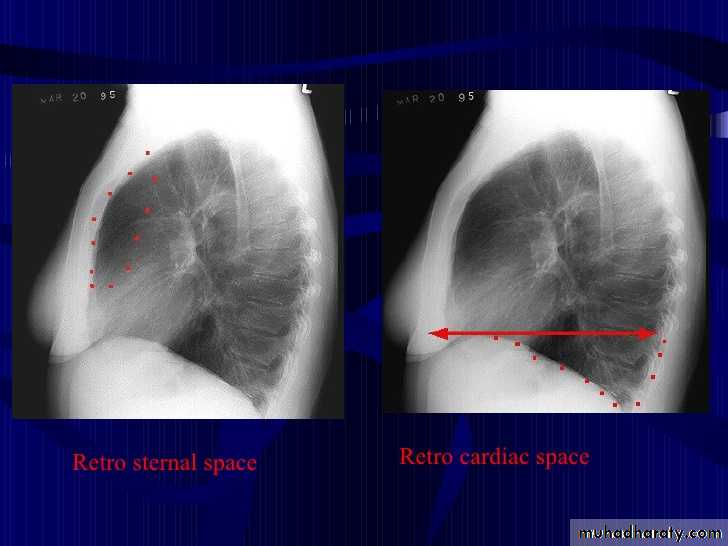

Lobes and fissures

This cut-out of a lateral chest x-ray shows the positions of the lobes of the right lung

On the left the oblique fissure is in a similar position but there is usually no horizontal fissure, and so there are only two lobes on the left.